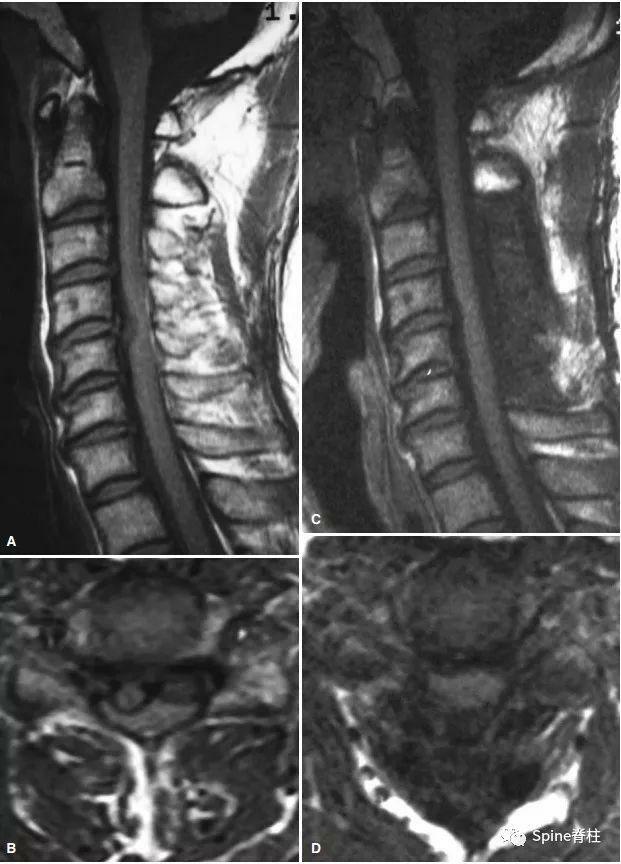

患者,女,40歲。因頸肩部不適4年加重伴行走不穩7d入院。起始頸椎MRI示:左側椎間盤突入中央管,嚴重脊髓壓迫(圖 1)。診斷為脊髓型頸椎病,建議患者入院行頸椎前路椎間盤摘除 cage 植骨融合內固定手術治療。患者拒絕手術,要求非手術治療,給予口服非甾體抗炎藥、神經 營養藥及肌松藥物治療,同時患者自行牽引、手法治療。3個月後患者症狀緩解。6個月後複查頸椎MRI顯示C5-6突出的椎間盤自發性吸收,突出的髓核消失 80%(圖 2)。